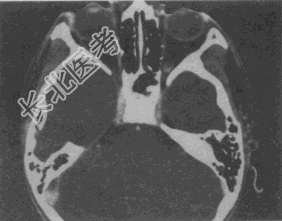

- 单项选择题女,46岁, 自述左眼视物不清约3个月,CT扫描如图所示, 正确的描述或诊断是

A、双侧眼球未见病变

B、左侧玻璃体内偏后方见絮状高密度影

C、双侧眼环形态密度正常

D、考虑视网膜脱离

E、考虑玻璃体内出血